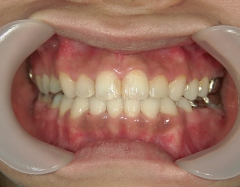

矯正歯科 治療後矯正歯科 全顎ワイヤー矯正 治療後矯正歯科(全顎ワイヤー矯正)治療後

全顎ワイヤー矯正 症例(18)

30歳女性 浜松市北区在住

治療期間3年4ヶ月

主訴:前歯の歯並びが気になる。

矯正歯科 治療後